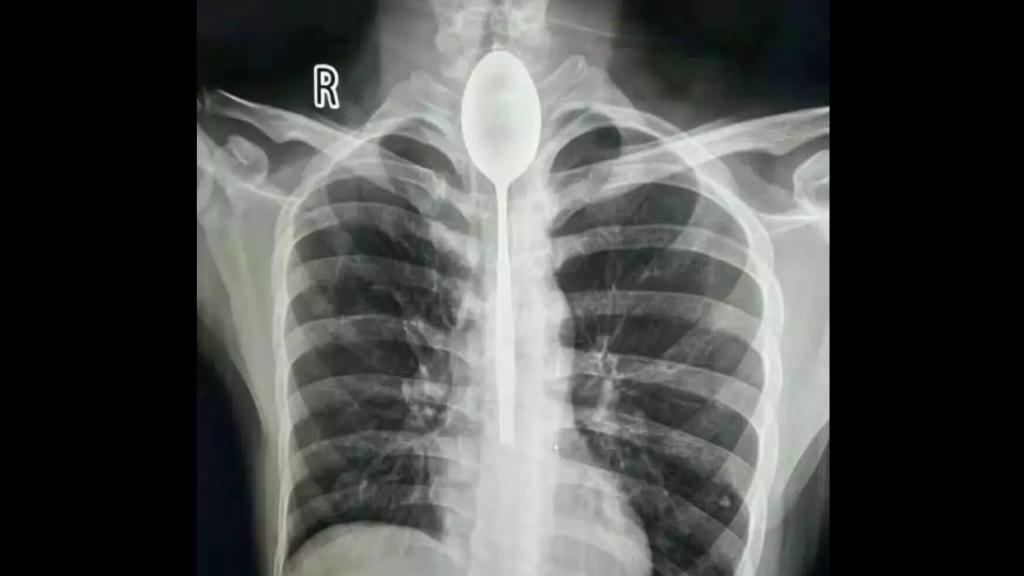

La radiografía con la cuchara alojada en el esófago del paciente.

Ese no fue el caso del Sr. Zhang, un veinteañero chino que se tragó una cuchara de metal por una apuesta durante 2017, la cual quedó atascada en su esófago, el "tubo" que une la cavidad oral y el estómago. Sin embargo, no debió provocarle demasiada molestia dado que no solicitó consulta médica hasta un año después, según relatan los medios locales.

Según los médicos que atendieron al paciente en el Hospital General de Xinjiang Meikuang, a pesar de que sufría cierta irritación esofágica, este hombre no solicitó ayuda hasta finales de octubre de 2018. En ese momento fue cuando empezó a padecer dolor en el pecho y dificultad para respirar tras haber sufrido un golpe en esa zona.

La hipótesis más probable es que el golpe desplazase el utensilio de metal, que fortuitamente y hasta entonces estaba colocado de forma a no interrumpir la respiración y la deglución. Fueron necesarios hasta tres médicos para retirar la cuchara tras dos horas de intervención, extrayendo el objeto de unos 20 centímetros de largo y recubierto de mucosidades.

Según el Dr. Yu Xiwu, director del Departamento de Otorrinolaringología del hospital, Zhang acudió sosteniéndose el pecho y relatando un intenso dolor. Cuando se le realizó una radiografía simple de tórax, se pudo objetivar la presencia de un cuerpo extraño de metal en la parte superior de su esófago. Posteriormente, mediante el uso de un endoscopio (un tubo largo con una cámara en su extremo), se pudo corroborar que se trataba de la cuchara cubierta de moco.